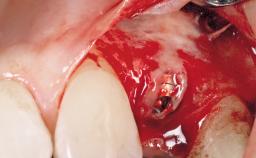

A 39-year-old male patient presented with a chief complaint of discomfort and gingival discoloration around his maxillary left central incisor. He was in good general health and was a non-smoker. His past dental history was significant because of the traumatic fracture of tooth 21 in a sporting accident at age 13. Initial dental treatment included endodontic therapy and a full-coverage restoration. The patient became symptomatic 5 years later, when structural failure of the tooth resulted in the dislodgment of the crown. Endodontic retreatment, apical surgery, and post-and-core restoration were performed.

| Bone Volume | Deficient horizontally, requiring prior grafting |